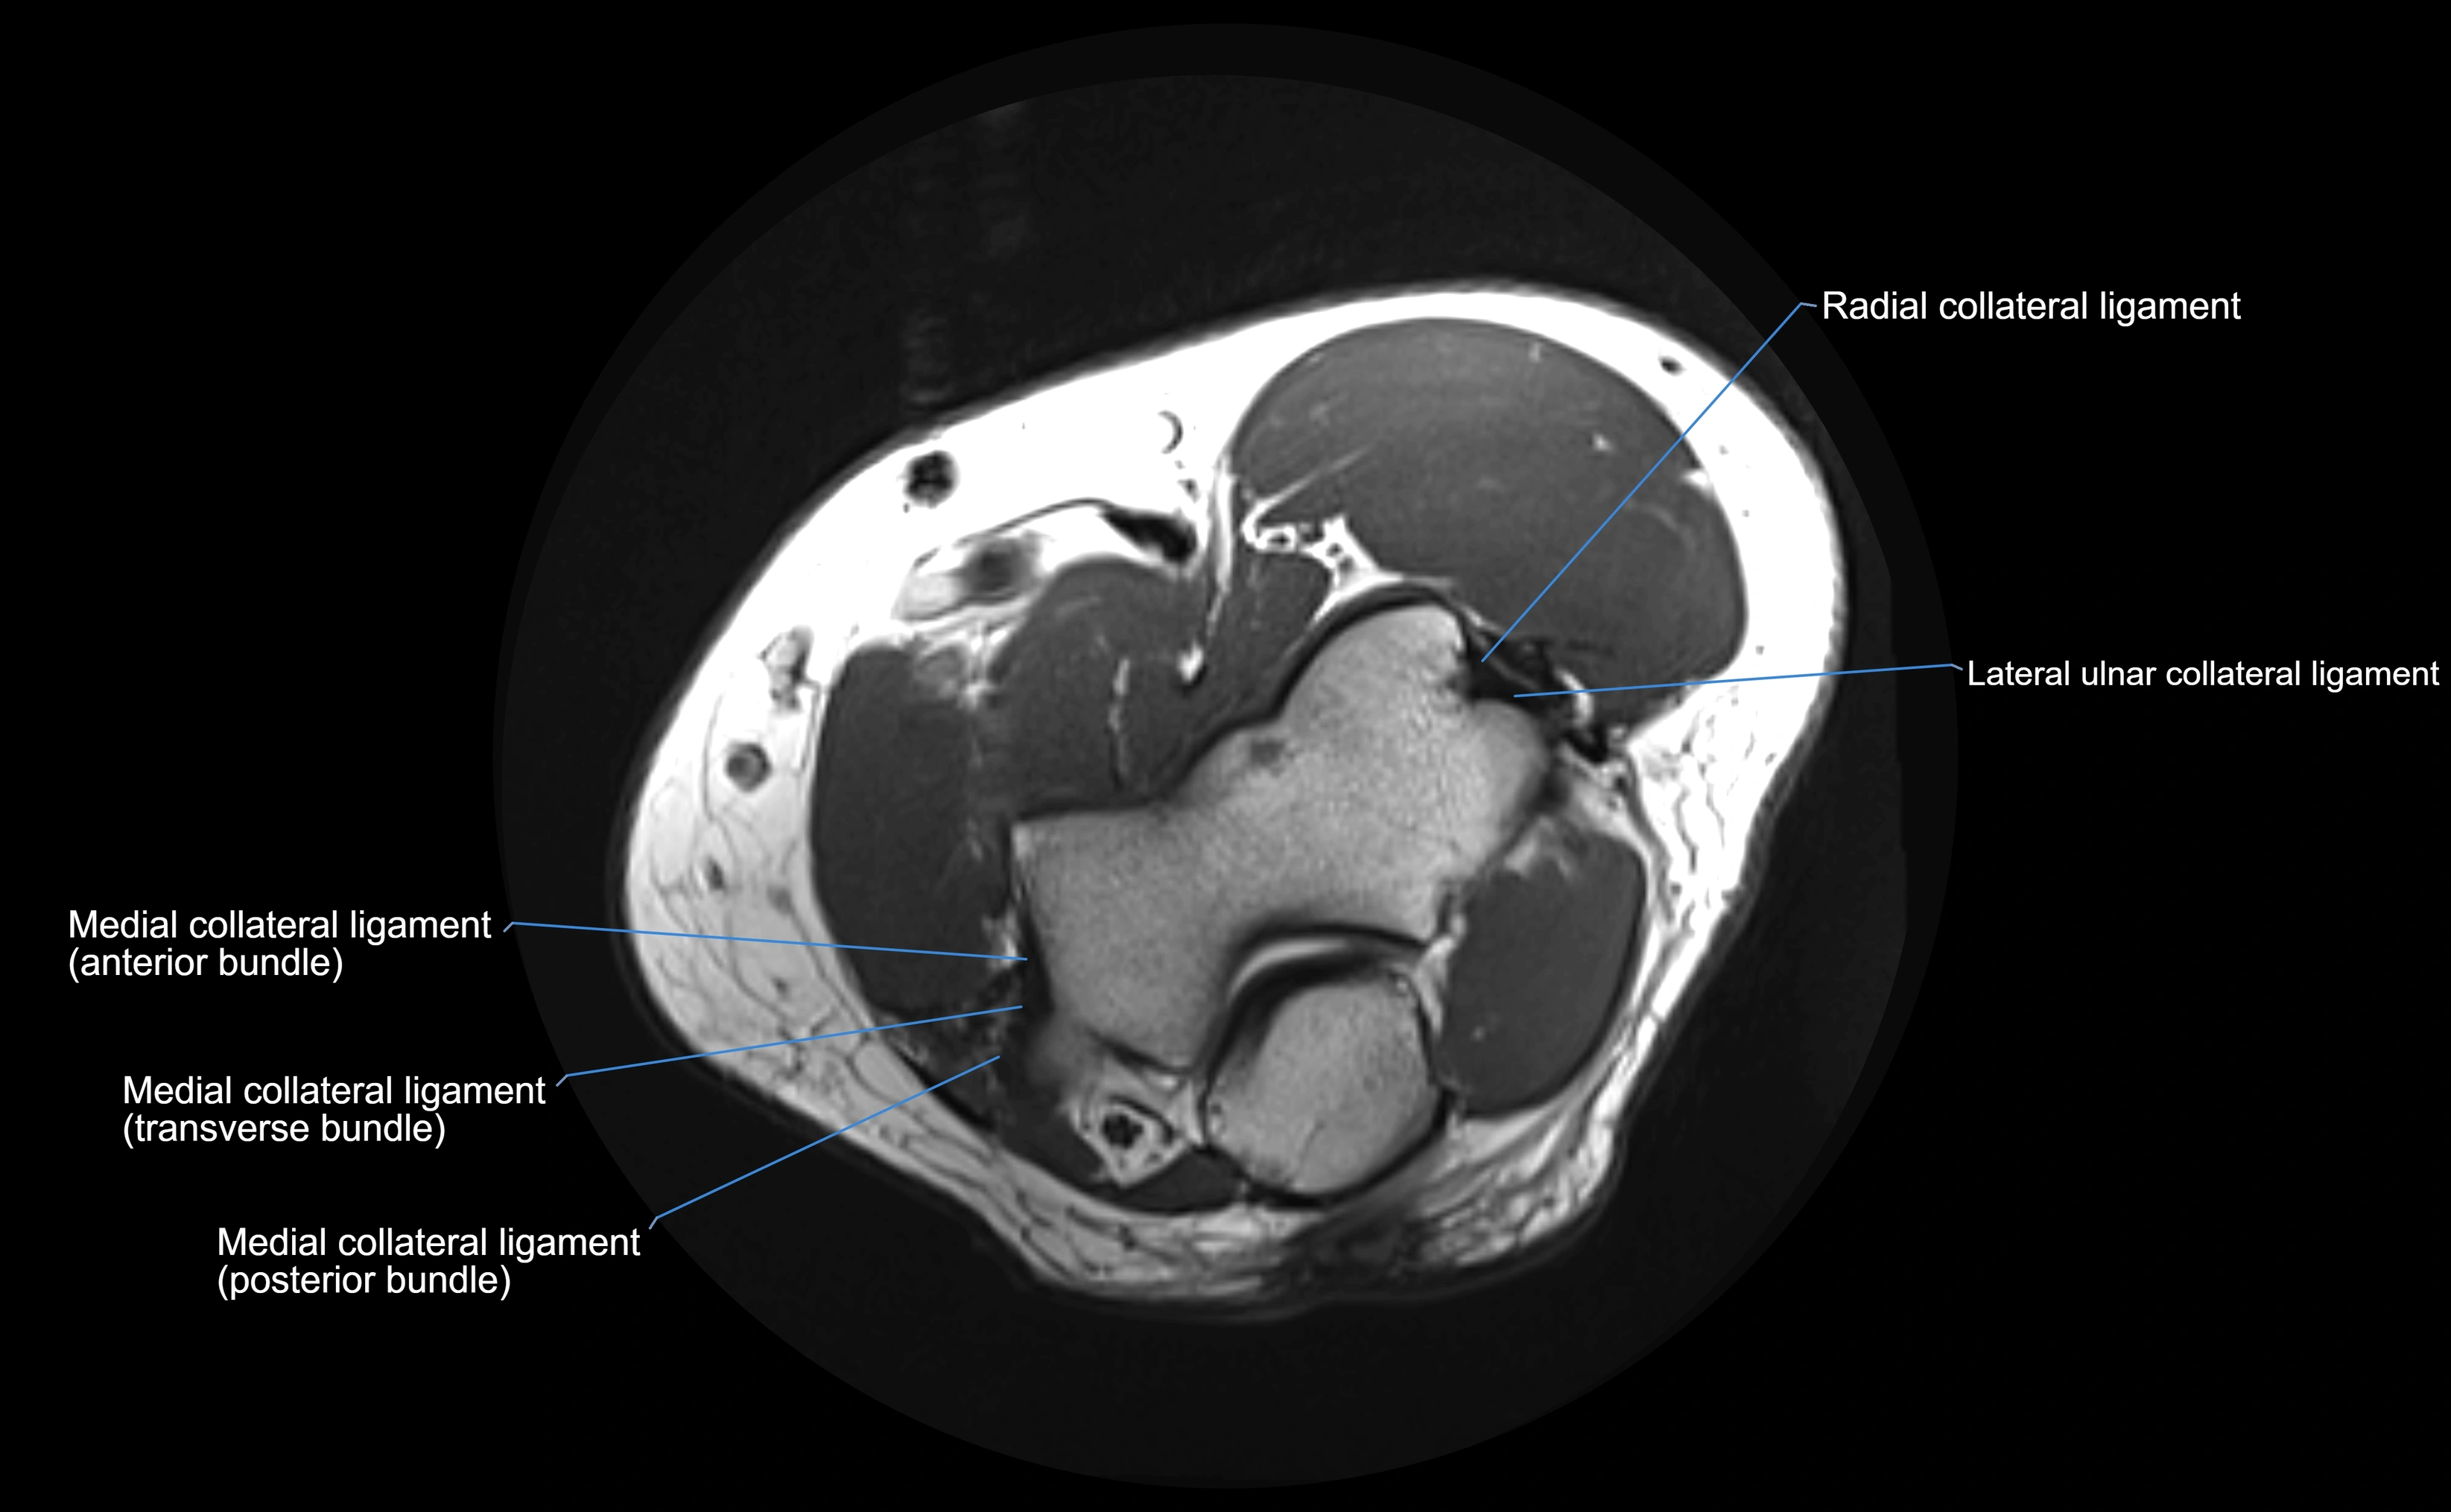

Origin, Course, and Insertion

• Origin: Arises from the anterior margin of the radial notch of the ulna.

• Course: Forms a strong circular band that wraps around the radial head and neck, maintaining them within the radial notch.

• Insertion: Attaches to the posterior margin of the radial notch, completing a fibrous ring around the radial head.

Relations

• Superiorly: Blends with the capsule of the elbow joint.

• Inferiorly: Supported by the quadrate ligament at the neck of the radius.

• Medially: Attached to the ulnar radial notch.

• Laterally: In contact with the radial head and its articular cartilage.

• Anteriorly: Related to the radial collateral ligament of the elbow.

• Posteriorly: Continuous with the elbow joint capsule.

MRI Appearance

T1-weighted images:

• Ligament: low signal intensity (dark), appearing as a continuous band around the radial head.

• Adjacent fat and marrow: bright, creating contrast with the ligament.

• Thickening or disruption indicates injury or fibrosis.

• Joint capsule and synovium seen as thin low-signal lines contiguous with ligament margins.

T2-weighted images:

• Ligament: low signal (dark) with clear delineation from joint fluid.

• Fluid or edema: bright hyperintense, separating or surrounding the ligament in partial tears.

• Complete tear: discontinuity or non-visualization of ligament fibers, often with joint effusion.